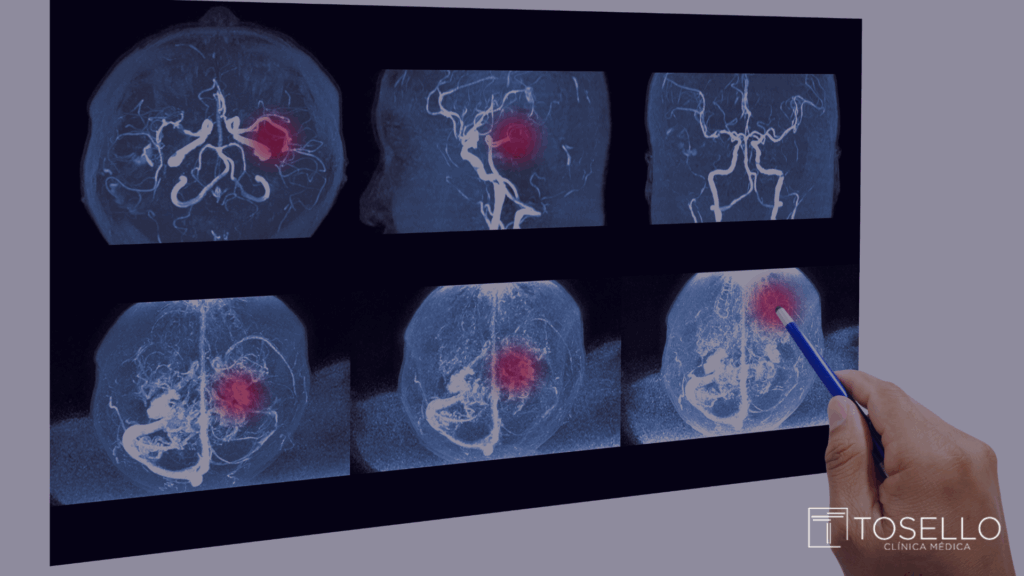

Quais exames ajudam a diagnosticar o aneurisma cerebral?

O diagnóstico do aneurisma cerebral é feito por meio de exames de imagem que permitem visualizar os vasos sanguíneos do cérebro. Entre os principais estão:

• Angiografia cerebral: considerado o exame padrão-ouro.

• Angiorressonância magnética arterial do crânio: método menos invasivo, mas altamente eficaz, para avaliação dos vasos sanguíneos, sem emissão de raio-X e sem uso de contraste.

• Angiotomografia computadorizada arterial do crânio:método menos invasivo, mas altamente eficaz, para avaliação dos vasos sanguíneos, com emissão de raio-X e com uso de contraste iodado.